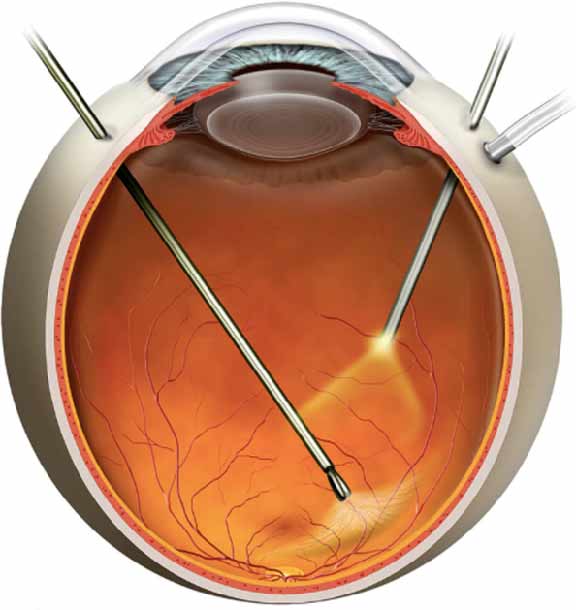

Refer below picture to understand more :

First, the vitreous jelly is removed (vitrectomy) and then a very delicate layer (the inner limiting membrane) is carefully peeled off the surface of the retina around the hole to release the forces that keep the hole open.

The eye is then filled with a temporary gas bubble, which presses the hole flat onto the back of the eye to help it seal.